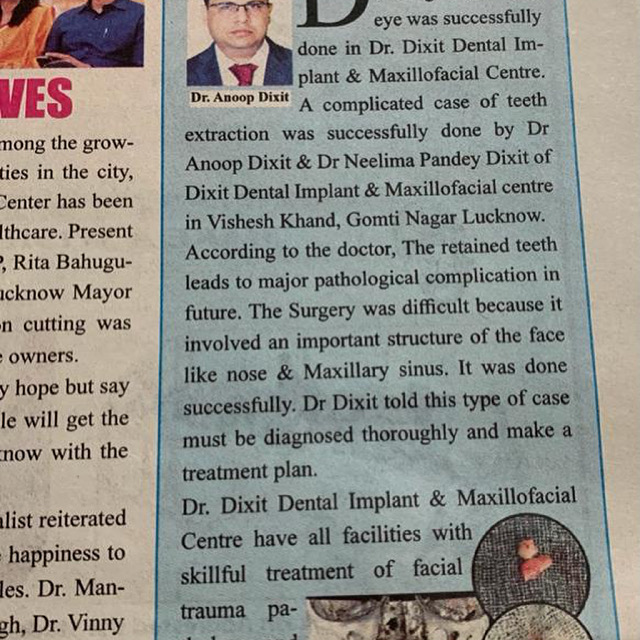

Dr. Anoop Dixit.

This clinic is running by Dr. Neelima Pandey Dixit & Team under the guidance of Dr. Anoop Dixit.